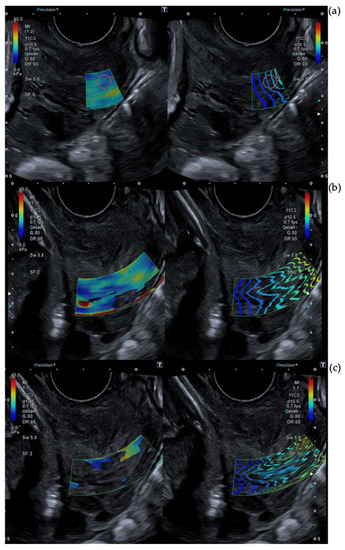

2.3. Cervical Shear Wave Elastography Measurement